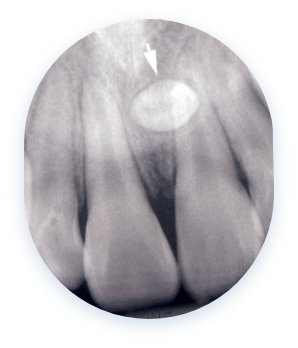

사랑니 물혹

사랑니가 매복된 경우,

치아와 잇몸 사이에 세균이 번식하여

충치 및 염증을 유발할 수 있습니다.

사랑니가 완전히 나오지 않고 잇몸에 덮여 있을 경우,

청소가 어렵고 음식물이나 세균이 쉽게 끼게 됩니다.

이로 인해 인접한 어금니에 충치가 생기거나 잇몸에 염증이 발생할 수 있습니다.

심한 경우 통증, 고름, 턱 붓기 등의 증상이 동반되기도 합니다.